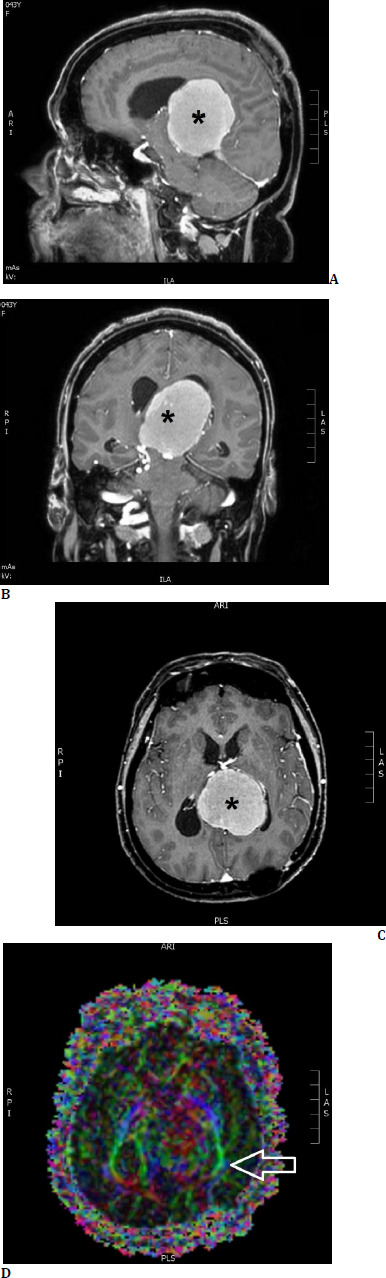

Objective: Intraoperative neuromonitoring (IONM) is nowadays a gold standard during brain tumor resections, but visual function mapping is less frequently performed in clinical practice. This article aims to report two transcortical brain tumor surgery cases affecting optic radiation, where the application of intraoperative visual evoked potentials (VEP) combined with tractography was beneficial to protect the patients' vision.

Methods: Two patients with brain tumors compressing the left posterior visual pathways underwent surgery under general anesthesia using IONM and VEP with neurologic improvement and preservation of vision.

Results: VEP is beneficial in the surgery of intra-axial lesions affecting the posterior visual pathways (optic radiation, visual cortex) and parasellar lesions involving the anterior visual pathways (chiasm). They can also be effectively combined with other mapping methods such as tractography.

Conclusions: According to our experience, IONM with VEPs and neuronavigation with tractography protect visual function in transcortical approaches to resecting tumors near the optic radiation and should be considered a standard monitoring method for such operations.